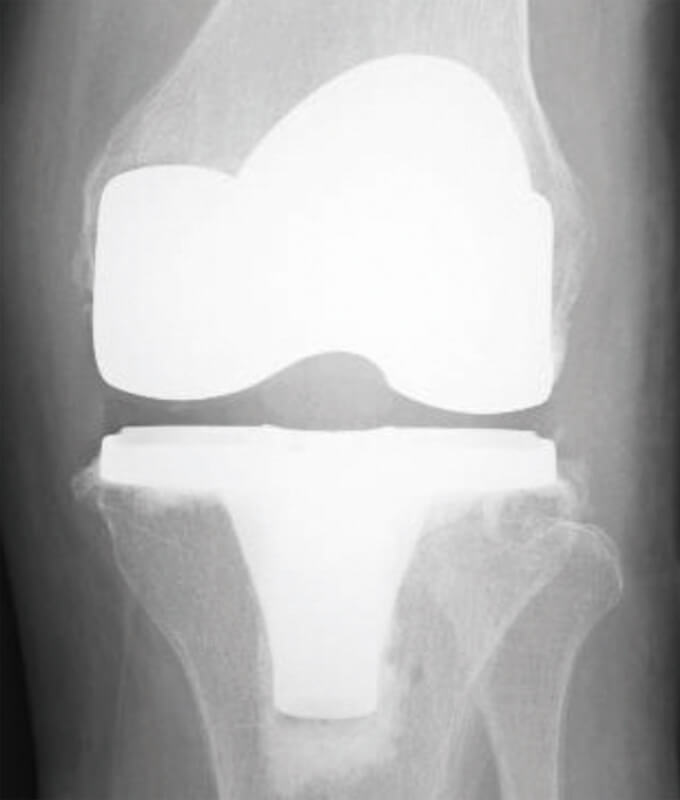

日本国内では、年間約8万人を超える人たちが人工膝関節手術を受けています。人工膝関節手術とは、痛んだ膝関節の一部分、あるいは全てを人工的なものと入れ替えて、膝の機能を回復する方法です。

人工膝関節

術後レントゲン